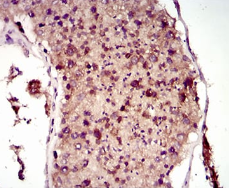

IHC    1/200 - 1/1000